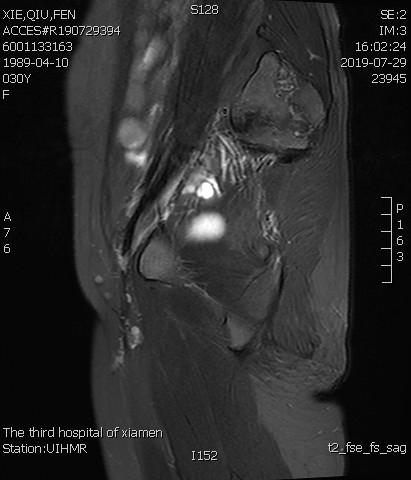

术后3个月复查MRI显示子宫明显缩小,前壁病灶萎缩坏死

术后复查MRI显示子宫明显缩小,腺肌瘤明显坏死吸收